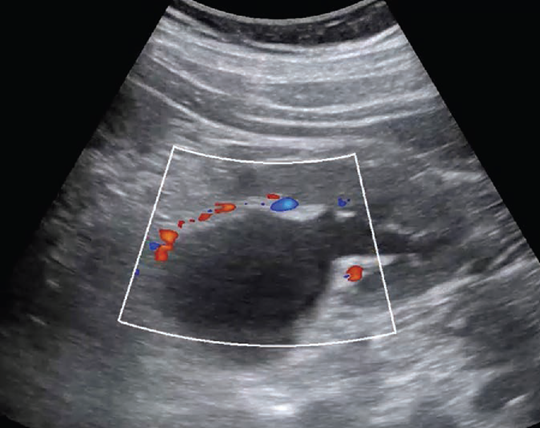

POCUS has excellent ability to detect AAA, which is defined by a diameter exceeding 3 cm when measured from outer wall to outer wall (Fig. 3).

A systematic review and meta-analysis found POCUS to have a sensitivity of 99% and specificity of 98%, when performed by emergency medicine physicians [23]. Although POCUS can accurately determine the presence or absence of AAA, the ability to detect signs of rupture is poor, which is largely due to the limited ability to visualize the retroperitoneum. Findings that indicate rupture include deformation of aneurysmal shape, heterogeneity or focal discontinuity of the intraluminal thrombus, focal disruption of the outer wall, hypoechoic areas in the paraaortic region, and hemoperitoneum [24].

POCUS is a great initial imaging option for suspected AAA, especially in the emergency department (ED), but adequate visualization may be limited by body habitus or bowel gas. The latter can be mitigated by graded compression, whereby slow, sustained pressure is applied to the abdomen to displace loops of bowel (and associated intraluminal gas) to allow better visualization of underlying structures. Like the FAST examination, AAA assessment is one of the core POCUS applications and is a required part of residency training for nonradiology specialties [10].